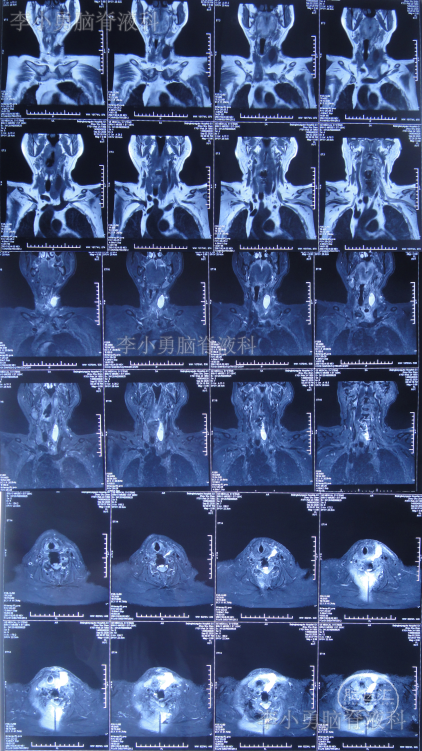

2020年8月13日(即第二次颈椎病术后第8天)患者开始出现颈部肿胀,床旁B超检查发现颈部切口深部积液,超声引导下穿刺抽出约87ml淡黄色透明液体,同时积液送细菌培养。2020年8月14日(即第二次颈椎病术后第9天)再次在床旁B超引导下穿刺抽液,抽出约90ml淡黄色透明液体,并加压包扎。复查颈部MR示术区皮下大量包裹性积液,考虑脑脊液漏(图-8)。

图-8:2020年8月14日颈部MR

2020年9月2日(入脑脊液科次日,即颈椎脑脊液漏修补术后第6天,即第二次颈椎病术后第25天)复查颈部MR示术区皮下深部仍有包裹性积液(图-10)。

图-10:2020年9月2日颈部MR